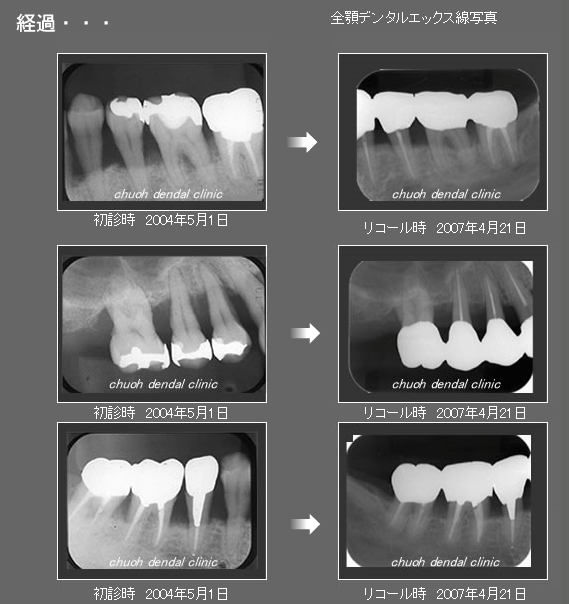

治療の特徴(患者T様)

平成13年7月7日 右下第一大臼歯頬側に膿瘍形成 著しい腫れ形成 著しい腫れ

- 男性33歳

- 平成14年11月9日 どうしても抜きたくないということで歯周外科処置する。

- その後H16から1~2カ月おきにメインテナンス。

- 平成16年6月11日 歯周治療により骨が出来てきています。

口の中から細菌を除去し、良好な環境を維持していくことによって歯周組織である歯槽骨や歯肉、歯根膜は生き生きとよみがえってきます。継続は力なりと申しますが根気良く治療を続けることで健康が回復し維持されます。

| 治療期間 | 4年7カ月 |